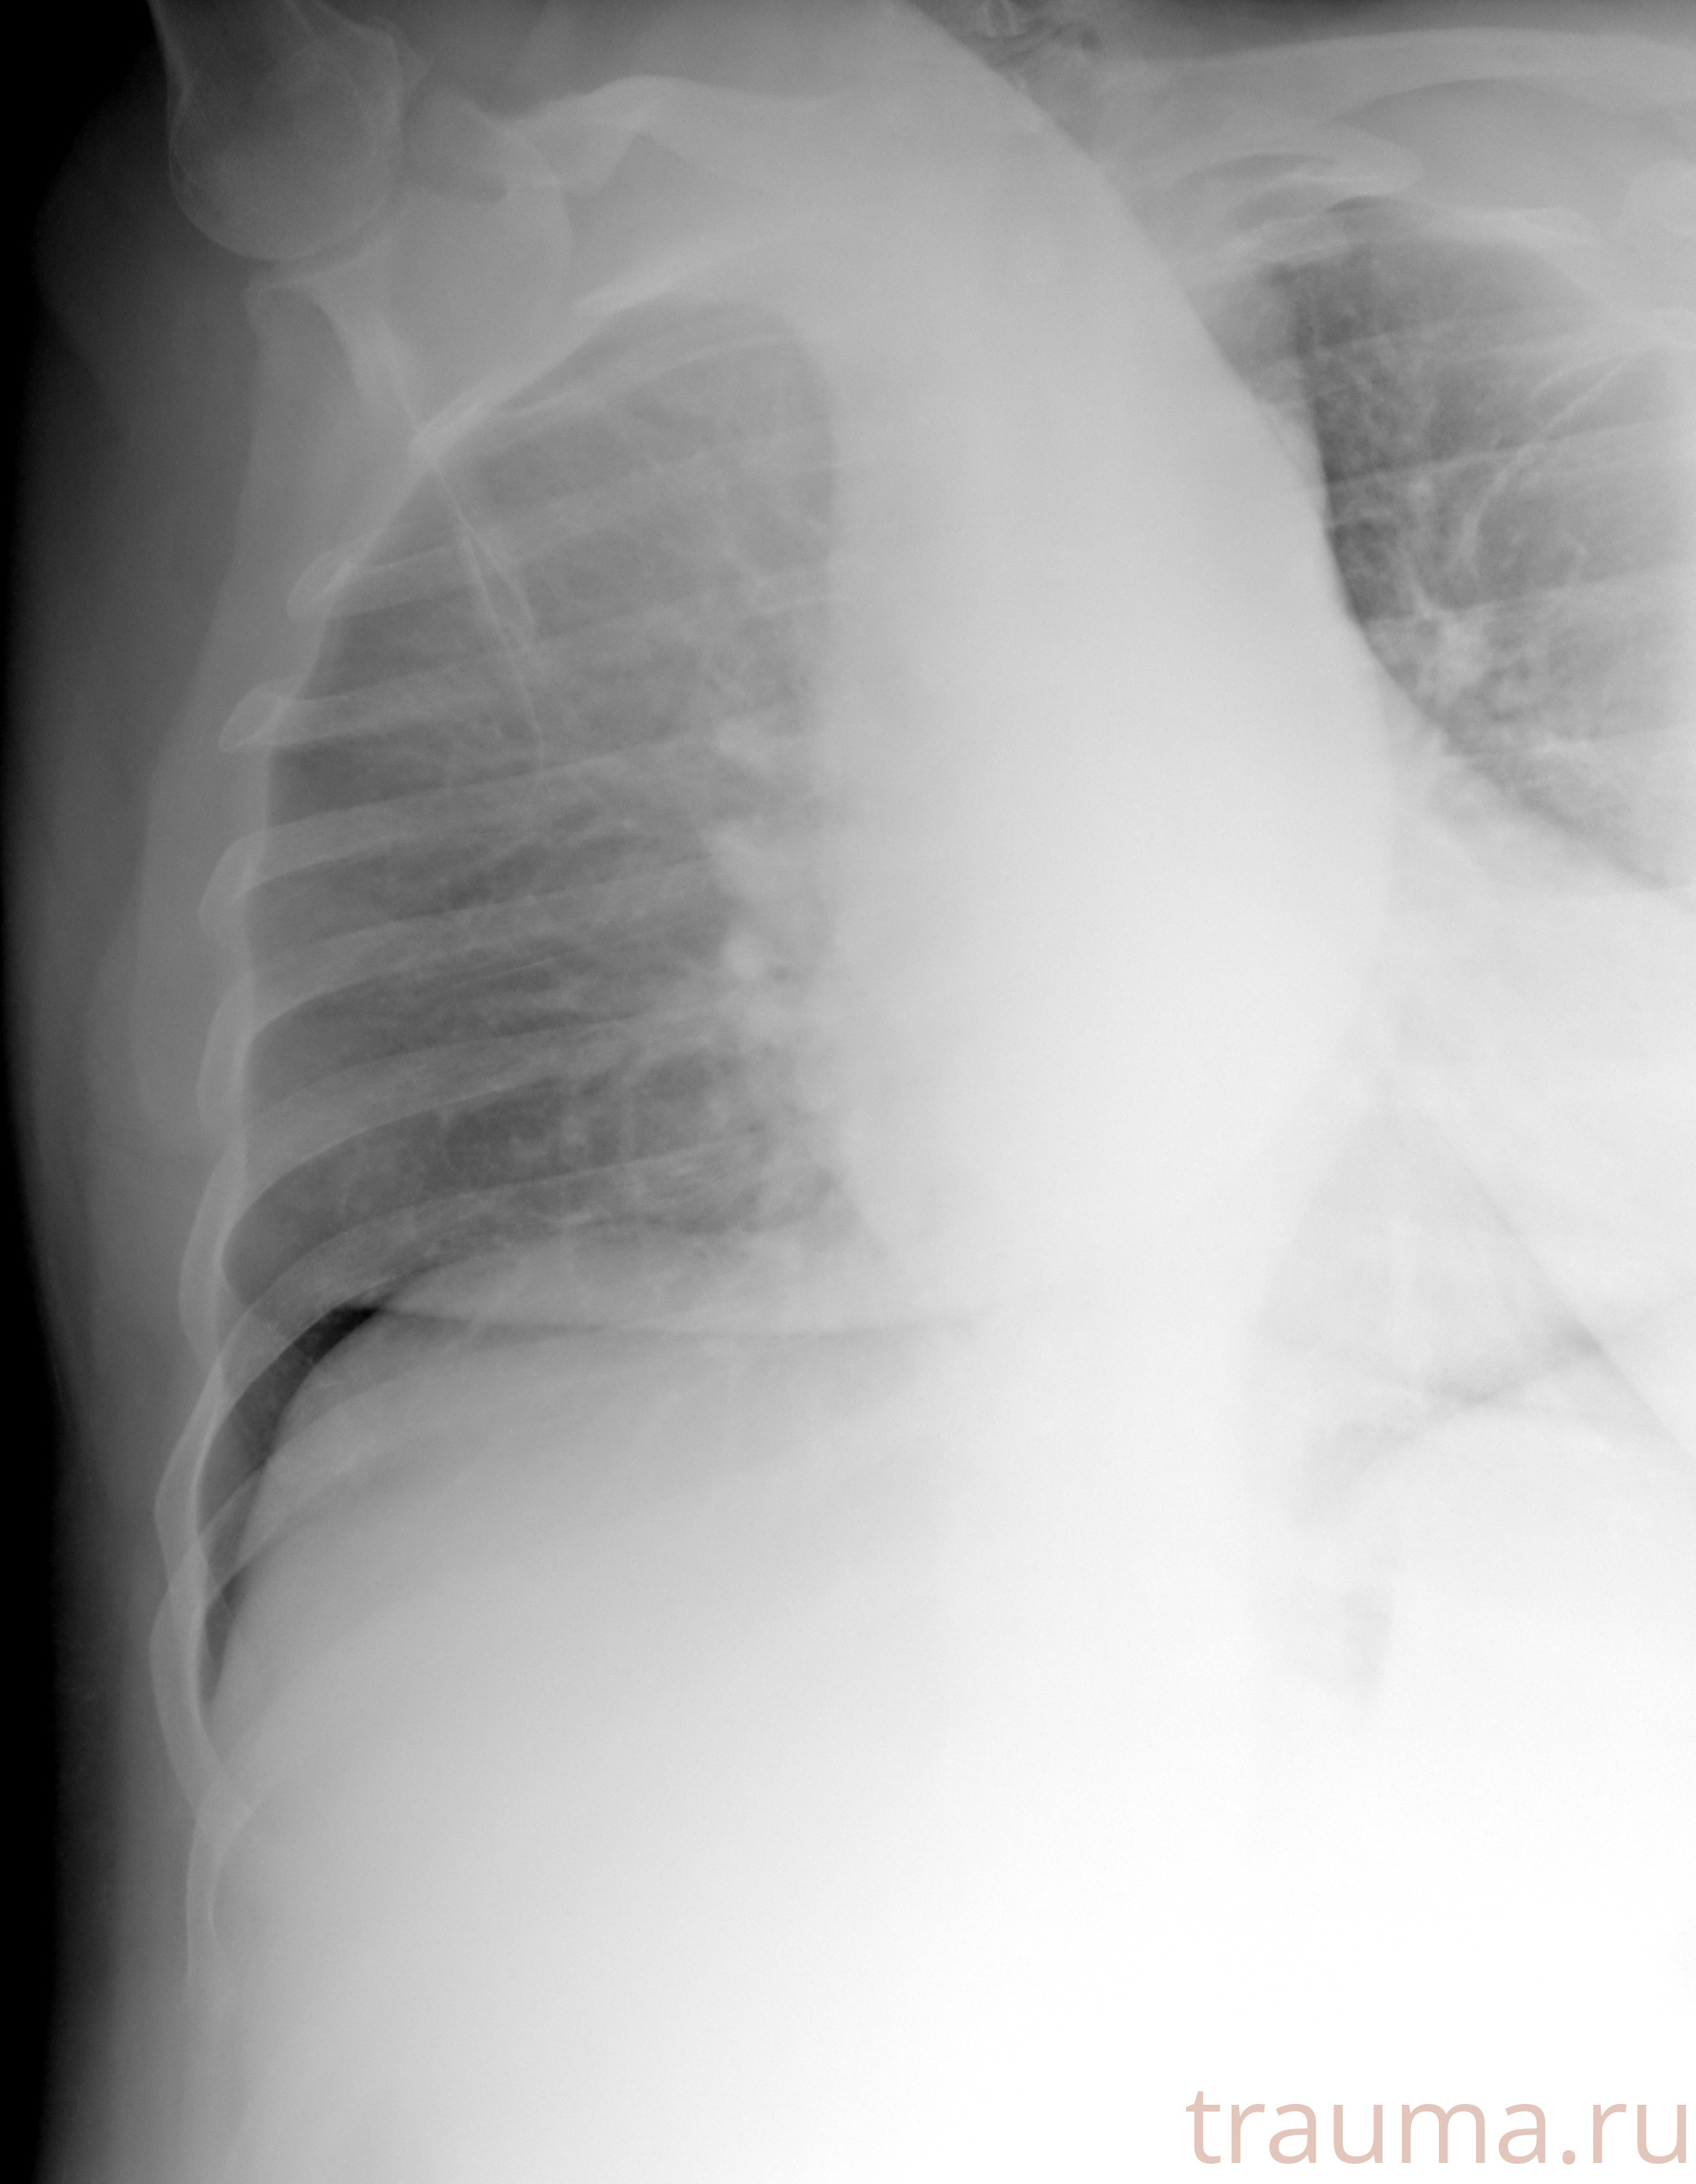

Рентген на дому: по вашему адресу приезжает врач-рентгенолог, травматолог-ортопед с мобильным рентгеновским аппаратом, проводит диагностику травмы или заболевания, делает необходимые рентгенограммы, дает рекомендации по дальнейшему лечению. Получить качественные снимки в домашних условиях возможно благодаря уникальной методике, разработанной МосРентген Центром для института  Склифосовского